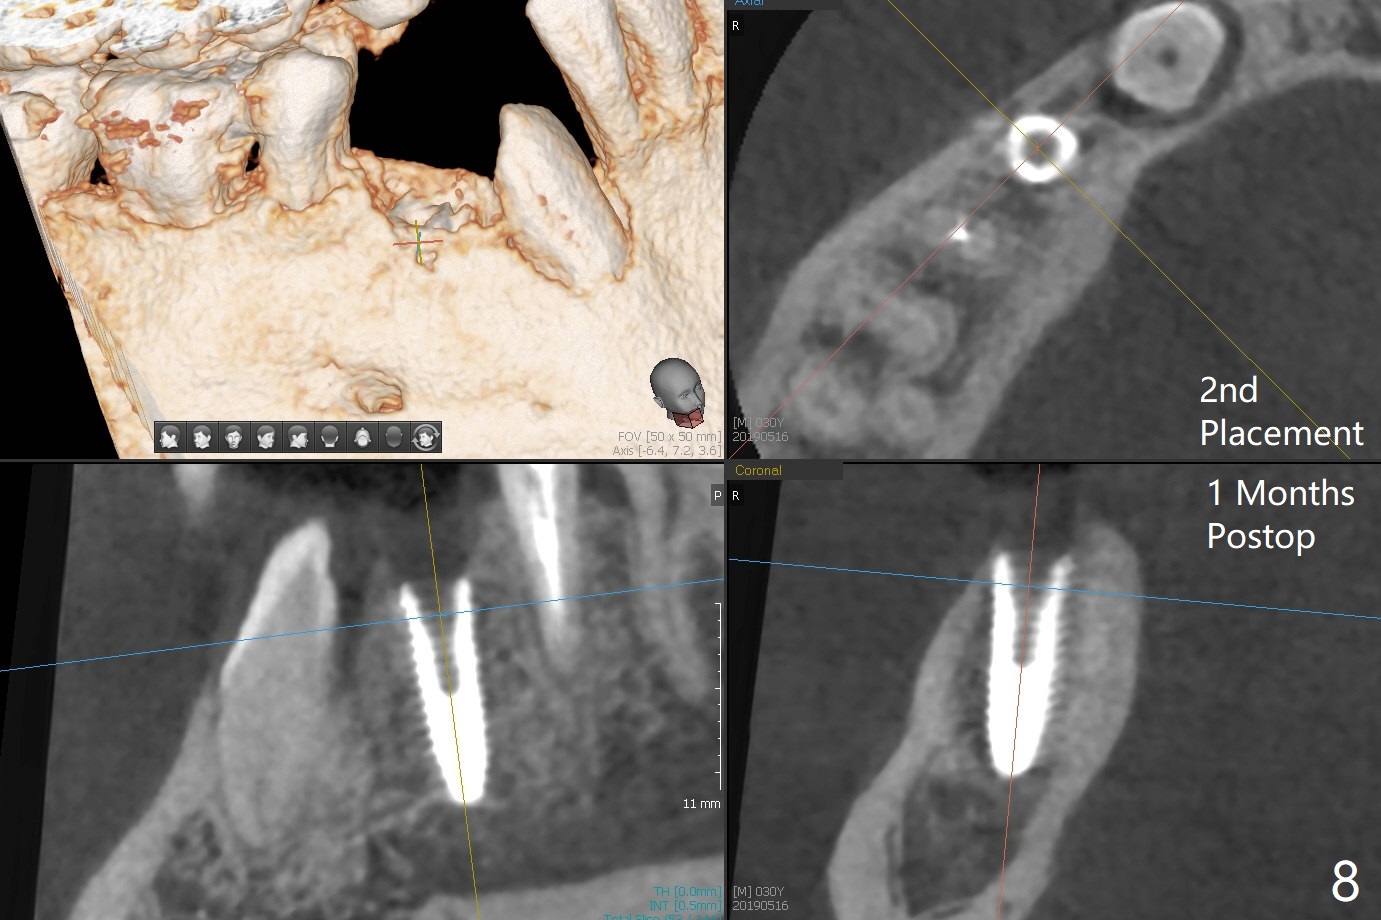

When the surgical guide for #28 is removed, the 4x13 mm implant is found to be superficial and buccal. Part of the buccal mucosa is nonkeratinized. After 1 mm deeper placement of the implant, CT confirms the buccal placement (Fig.1, as compared to design). In fact the guide was doubly checked for fitness prior to osteotomy, but grossly it seemed to be seated properly. The suspicion is related to the trimming at the site of #27 (Fig.2,3 (*), as compared to a mounted model in Fig.4,5 (arrowhead) and the model sent to lab for guide fabrication). The lab agrees to redesign the case. There is a narrow buccal band 1 week postop (Fig.6). The patient is a smoker. The implant was placed buccal (Fig.7, 1 month postop). A new 4x13 mm implant is placed on the top of the 1st line following 3x14.5 mm drill (Fig.8 (35 Ncm)). In fact the implant position is not changed much. Four months post banding (20 ss) and 2 months post 2nd implant placement, the tooth #27 is exposed for bracket; extrusion is initiated (Fig.9). In 3 weeks of retraction, the bracket is supragingival (Fig.10). The canine contacts the distal healing abutment with 2 months of retraction (Fig.11). It seems necessary to initiate lower bracket placement. There is no bone loss 4 months postop (Fig.12). A 4.5x7(4) mm abutment is placed (Fig.13) for a temporary crown as an anchor (Fig.14) to further extrude #27 with continuous inter-arch retraction (to reduce tension upon #26 with severe bone loss (Fig.12)). LR3 extrusion is incomplete, although there is an increase in bone distal to LR2 ~ 10 months of extrusion (Fig.15).